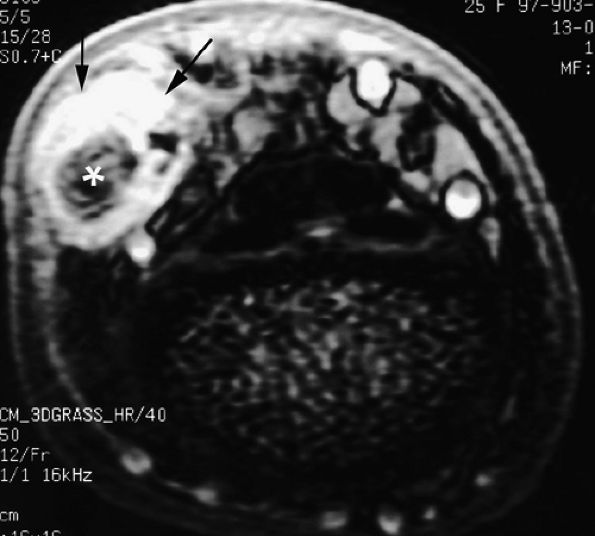

![]() |

|

FIGURE 11.60 ● Posttraumatic arteriovenous fistulas. Axial post-contrast 3D gradient-echo image shows peripheral enhancement (arrows) and a central flow void (asterisk) due to high velocity.